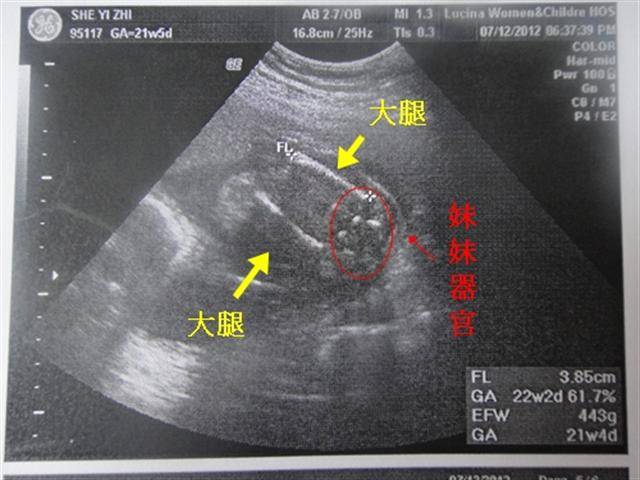

【小龍寶寶】懷孕22W2D‧是漂亮的小女娃

2012/07/12

22W2D

去做了高層次超音波

不過這間婦產科好小氣

收費$3000居然是2D

(在那生之後會退$1500)

要照3D還要另外收費

沒有小雞雞

確定是妹妹了